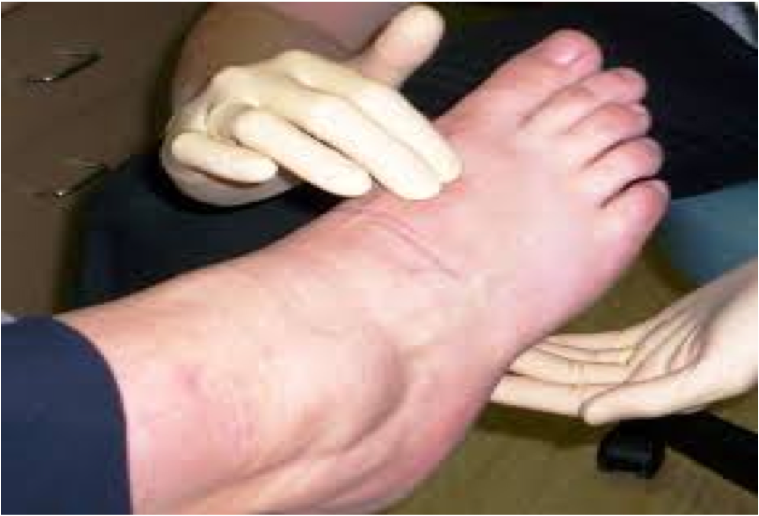

C: moderately swollen R thigh w/ anterior ecchymoses, cold and pale distal extremity w/o palpable pulses, RLE ttp throughout

Lower Arterial Trauma (EAST)

- Level 2: Patients w/ hard signs of arterial injury should be surgically explored (no imaging). No need for CTA unless associated skeletal or shotgun injury. Restoration of perfusion in < 6 hrs to maximize limb salvage.

Hard Signs of Arterial Injury

- Pulsatile bleeding

- Expanding hematoma

- Absent distal pulses

- Cold and pale limb

- Palpable thrill

- Audible bruit